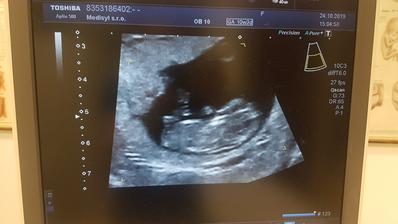

Zatial tajne dúfame,že všetko dobre dopadne..

...druhé šťastie...

Doslova..